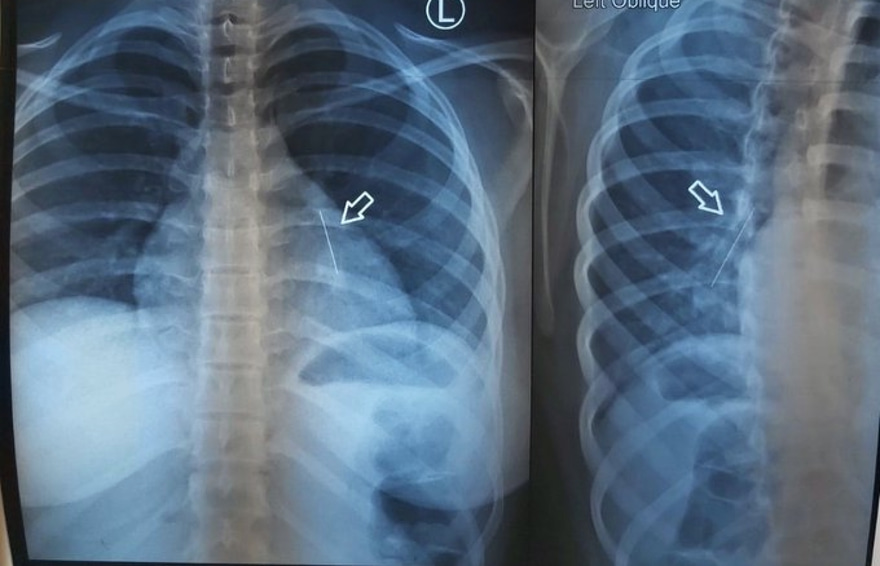

މިދިޔަ އަހަރުގެ ޖުލައި މަހުގެ ތެރޭގައި، ކާއެތިކޮޅު ތާށިވެގެން، އުމުރުން ފަސް އަހަރުން ދަށުގެ ކުއްޖާ އެންމެ ފުރަތަމަ ގެންދިޔައީ އައިޖީއެމްއެޗަށެވެ. ރޯގާ ޖެހި ނޭވާލާން އުނދަގޫވާތީ، އެންމެ ފުރަތަމަ ހެދީ އެ ކުއްޖާގެ ސީޓީ ސްކޭނެކެވެ. ނޭވާލާ މައި ހޮޅިއަށް ވުރެ ވެސް އެތެރޭގައި ކާއޭތިކޮޅު ތާށިވެފައިވާކަން އެނގުނީ އެ ސްކޭނުންނެވެ.

ނޭވާލާހޮޅީގައި ތާށިވެފައިވާ ކާއެތިކޮޅު ނެގުމަށް އައިޖީއެމްއެޗުގެ ޑޮކްޓަރުން ވަރަށް މަސައްކަތް ކުރި އެވެ. ގަނޑުކޮށްގެން ވެސް އެ އެތިކޮޅު ނުނެގުނު އިރު، އެކަމުގެ ތެރޭގައި ކުއްޖާގެ ހާލު ސީރިއަސްވެ، ވެންޓިލޭޓަރުގައި ވެސް ބާއްވަން ޖެހުނެވެ.

އެންމެ ބޮޑު މައްސަލައަކަށް ދިމާވީ، ކާއެތިކޮޅަށް ގިނަ ދުވަސްވެ މަސް އަރާފައި އިނުމެވެ. އެހެންވެ، ޑޮކްޓަރުން ނިންމީ ކުއްޖާ ރާއްޖޭން ބޭރަށް ފޮނުވާލާށެވެ.

އައިޖީއެމްއެޗުގައި ކުޑަކުއްޖާ ބެލި އެތެރެހަށީގެ ޑޮކްޓަރު މުހައްމަދު އަލީ މިއަދު ވިދާޅުވީ އިންޑިއާގައި ދެ ފަހަރެއްގެ މަތިން ބްރޮންކޮސްކޮޕީ ނުވަތަ ފުއްޕާމޭގެެތެރެއަށް ހޮޅިއެއް ވައްދައިގެން، ކާއެތިކޮޅު ނަގައިފައިވާ ކަމަށެވެ.

"ކާއެތިކޮޅު އިނީ ވަރަށް އެތެރޭގައި. އަޅުގަނޑުމެން ފުރަތަމަ މަސައްކަތް ކުރީ ވެސް، ބްރޮންކޮސްކޮޕީ ހަދައިގެން ކެމެރާ ލައްވައިގެން އެ އެތިކޮޅު ނެގޭތޯ. އެކަމަކު އެތިކޮޅު ތާށިވެފައި އޮތް ހިސާބަށް ދެވޭވަރުގެ އެހާ ކުޑަ ސައިޒުގެ [ބްރޮންކޮސްކޮޕީ]އެއް އަޅުގަނޑުމެން އަތަކު ނެތް،" ޑޮކްޓަރު ވިދާޅުވި އެވެ.